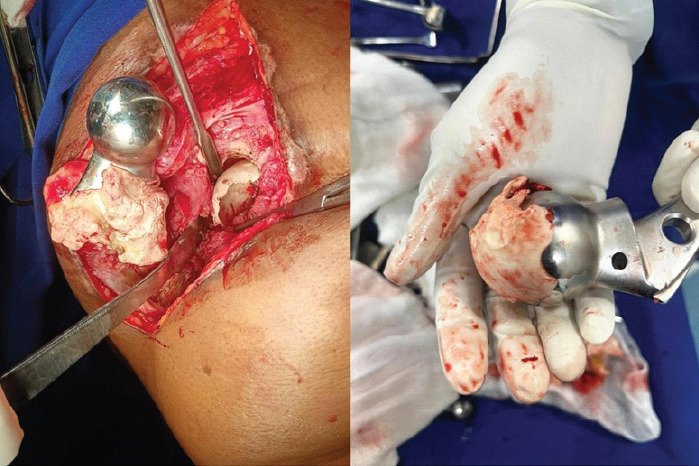

Case report: A 76-year-old woman presented 8 months after left hemiarthroplasty with persistent hip pain and immobility. She had become bedridden 1-month post-surgery following a sensation of hip slippage. Examination revealed limb shortening, adduction deformity, and restricted mobility. Radiographs showed a dislocated hip and multiple dense opacities in the acetabulum, suggesting cement interposition. A posterior approach revision was planned. Pre-operative skin traction and adductor tenotomy were performed to address soft tissue contractures. Intraoperatively, well-formed cement mass conforming to the acetabulum was removed. The cement was removed en bloc, and a bipolar prosthesis was implanted. Post-operatively, the patient achieved satisfactory recovery with improved hip stability and function.

Discussion: This case illustrates the potential for cement to migrate into the acetabulum during stem insertion if introduced pre-maturely or in excess. Such interposition disrupts joint articulation and can lead to chronic dislocation. Preventive steps - such as waiting for appropriate cement consistency, using a gauze barrier in the acetabulum, and careful intraoperative assessment - are critical to avoid such outcomes. Chronic dislocations further complicate surgical revisions due to soft tissue contractures and biomechanical imbalance. Comprehensive pre-operative planning and soft tissue management, combined with appropriate implant selection, contributed to successful revision in this case.